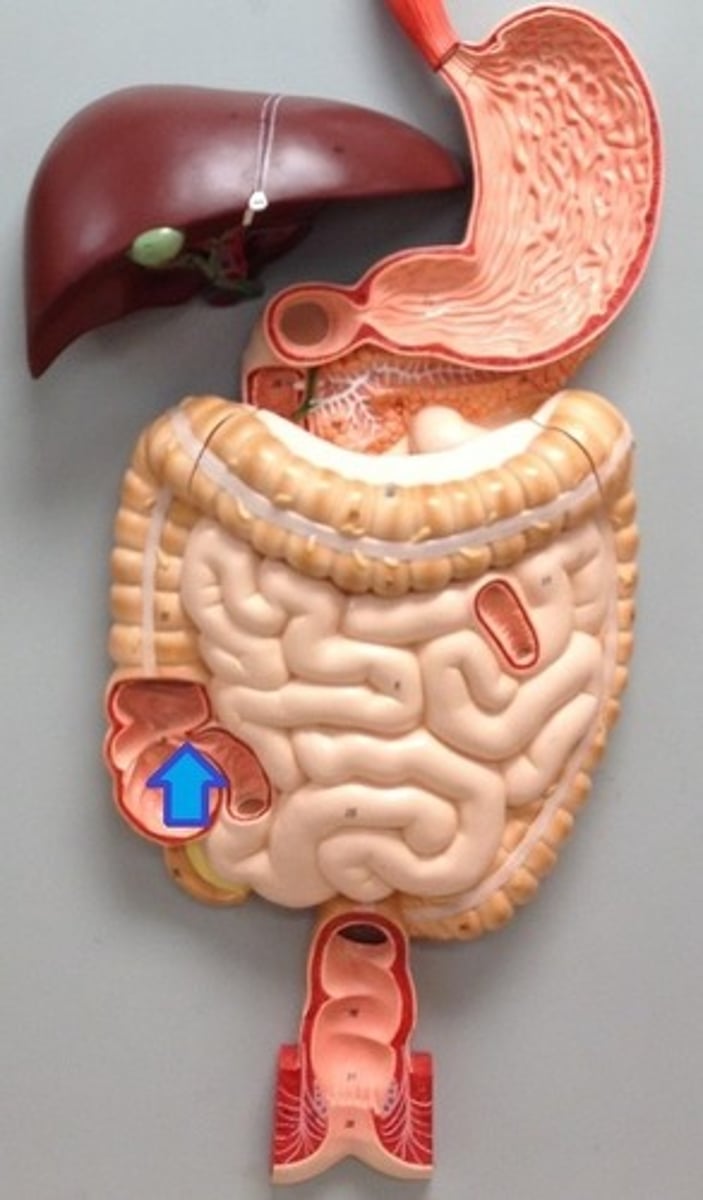

ileocecal orifice

large intestine

vermiform appendix

cecum